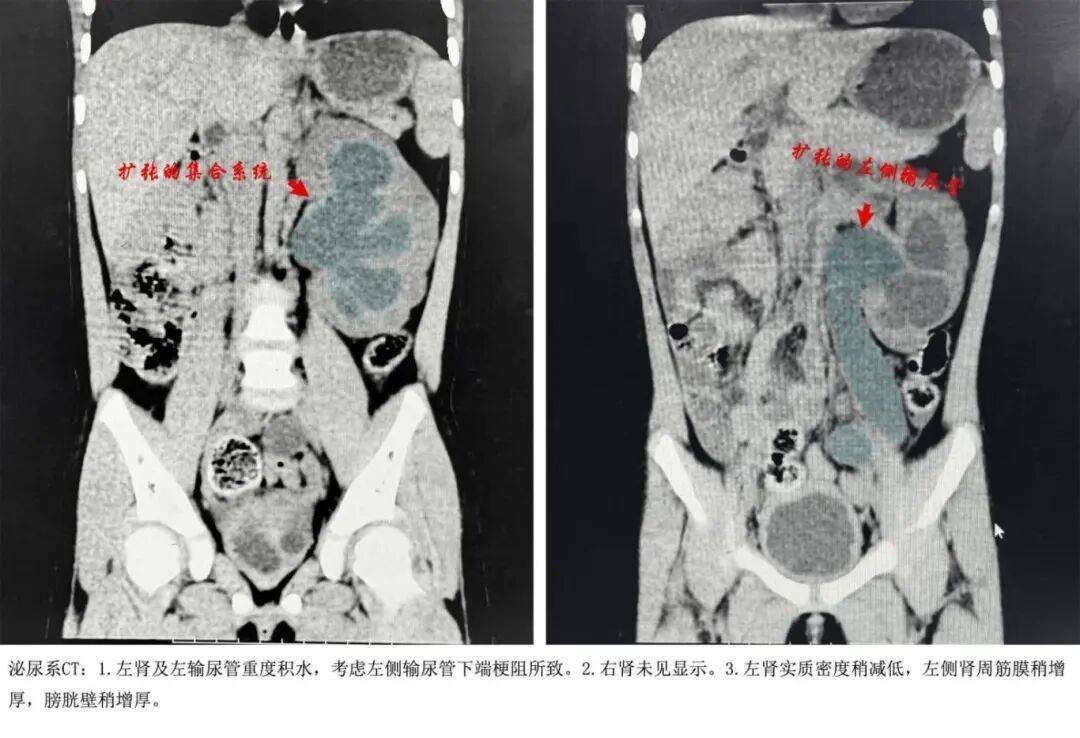

魏(wei)剑圣安排急查泌尿系CT平(ping)扫(sao)

提示左肾及左输尿管重(zhong)度积水

考虑左侧输尿管下(xia)端阻塞

医生检查发明,悄悄的脸浮肿(zhong),左上腹一按就疼,膀(bang)胱却是空的。彩色B超报告让人倒吸一口凉气——体内只发明一个左肾,而且左肾重(zhong)度肾积水伴输尿管全程(cheng)扩大,尿液排出的独一路径(左侧输尿管)堵住(zhu)了。